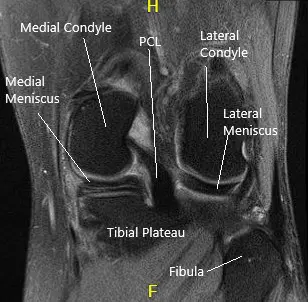

MRI of the left knee suggested tear of the posterior horn and posterior horn/body segment junction medial meniscus, with mild meniscal extrusion into the medial gutter and mild chondromalacia patella.

MRI of the knee in sagittal and coronal sections